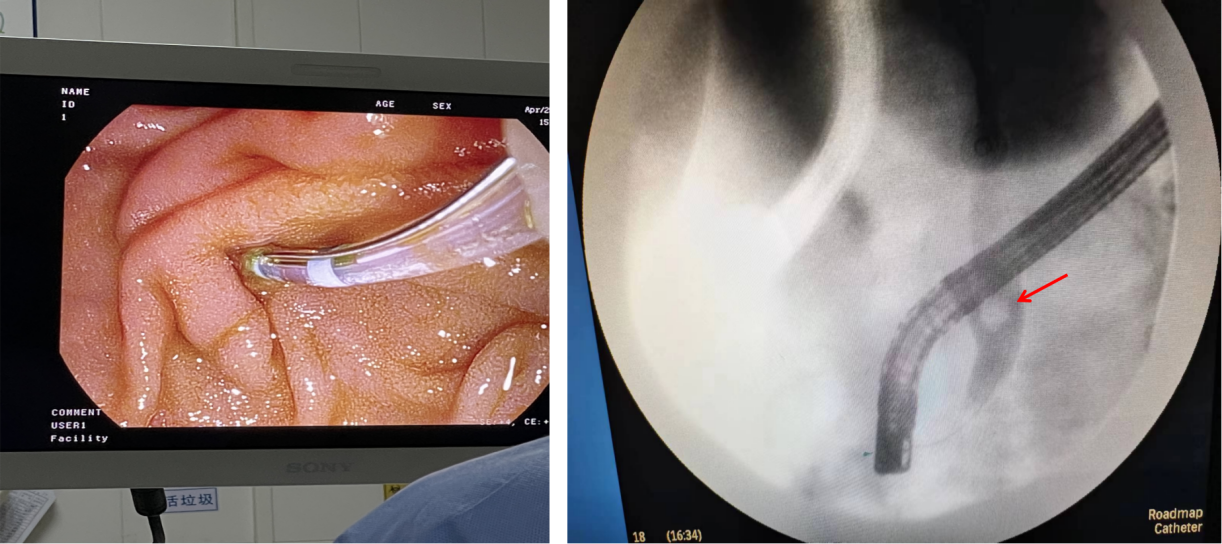

▲ 手术现场

手术当天,在内镜室负责人郭毅、介入科副主任庄学龙、麻醉科副主任李义贤、黄小燕主治医师及介入手术室廖贤英主管护师的大力支持和默契配合下,历时不到1小时,便将患者胆总管结石顺利取出,手术顺利完成。

▲ 十二指肠镜下找到十二指肠乳头,插入导管并造影显示胆总管结石(红色箭头所示)

▲ 胆总管结石顺利取出,掉入肠道(红色箭头所示)